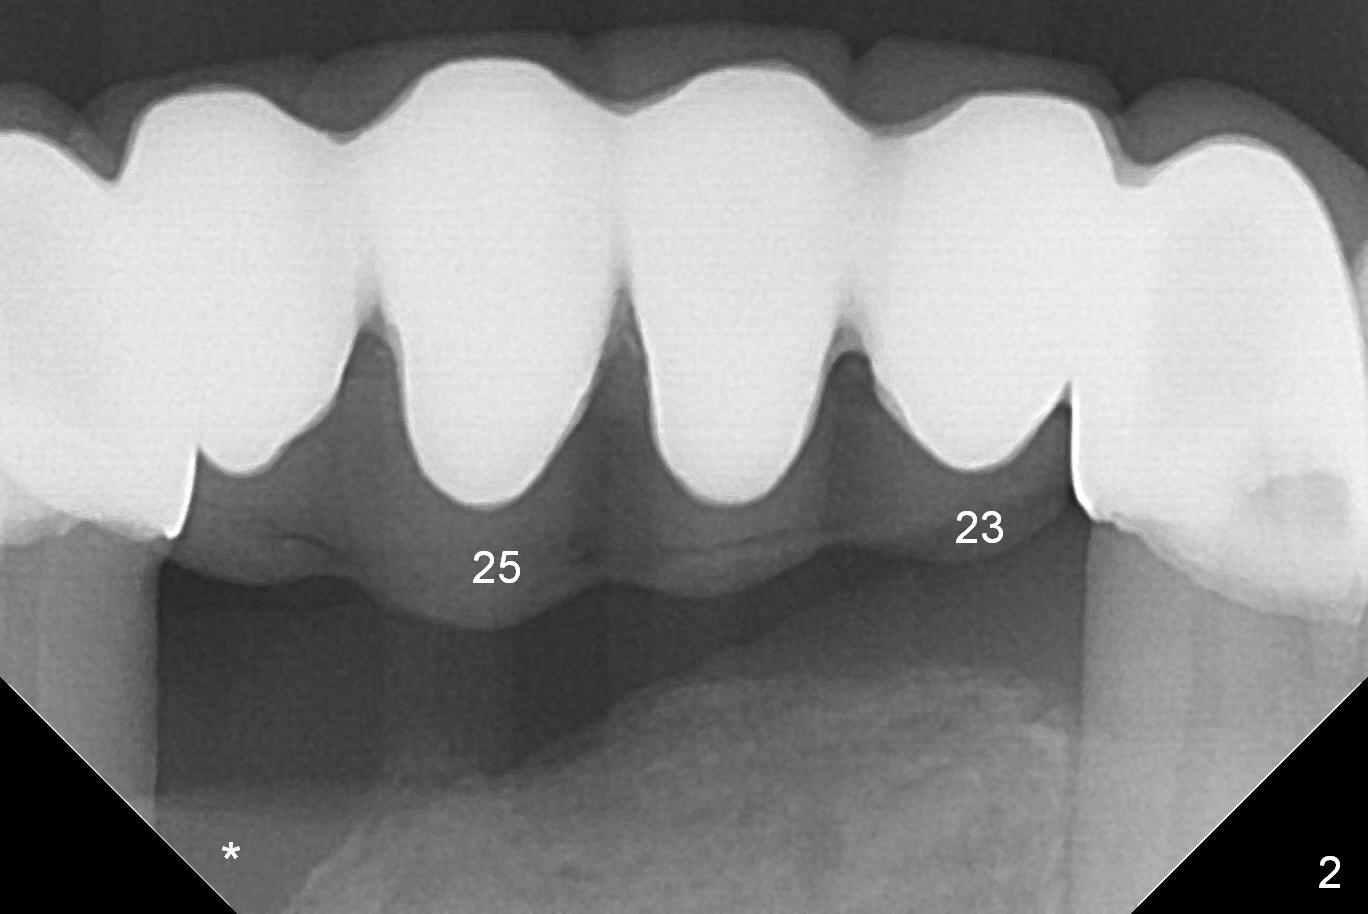

A 57-year-old woman has a 20-year-old loose FPD (fixed partial denture, Fig.1-3).  Upon Alginate impression for stent, the 6-unit FPD was dislodged with the exfoliated abutment at #27.  After removal of calculus from the root of #27, the FPD was placed in situ and temporarily cemented to #22 abutment.  When the patient returns, remove the FPD, treat the socket of #27 with Clindamycin, place implants at #23, 25 and 27 and fabricate a 6-unit provisional FPD.  At definitive stage of restoration, fabricate a 4-unit FPD at #24-26 and a single unit at #27.  Since bone loss is more severe mesiobuccally at #27 (Fig.1), place an implant as lingual as possible, but slightly more mesially.  If the defect is so severe that the implant (green) has to be placed deep, the abutment margin with the longest cuff (5 mm, pink) is less likely to contact the distal crest (*).  Crown margin (i.e., abutment margin of an implant) should be 2 mm more coronal to the crest normally.  The condition that does not meet the requirement is called violation of biologic width, associated with periodontitis or periimplantitis.